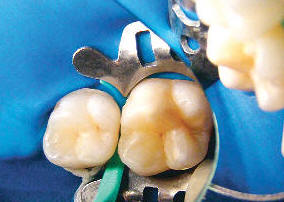

Después de aislar el diente con un dique de goma y la colocación de cuñas para separar los dientes, la superficie del diente se prepara con un 15% de gel de HCL para abrir el sistema de poros del cuerpo de la lesión . A continuación, la superficie se enjuaga y  se seca con etanol, luego se continua secando con aire a presión. La resina Infiltrante Icon, que tiene un coeficiente de penetración alto, se aplica sobre la lesión, el exceso de material se retira, y el material es curado por luz. El fabricante recomienda la aplicación de una segunda capa del infiltrante, seguido de curado por luz adicional.

Aislación y separación de dientes

Gel de HCL

Se enjuaga y se seca con etanol

Resina infiltrante

Fotocurado